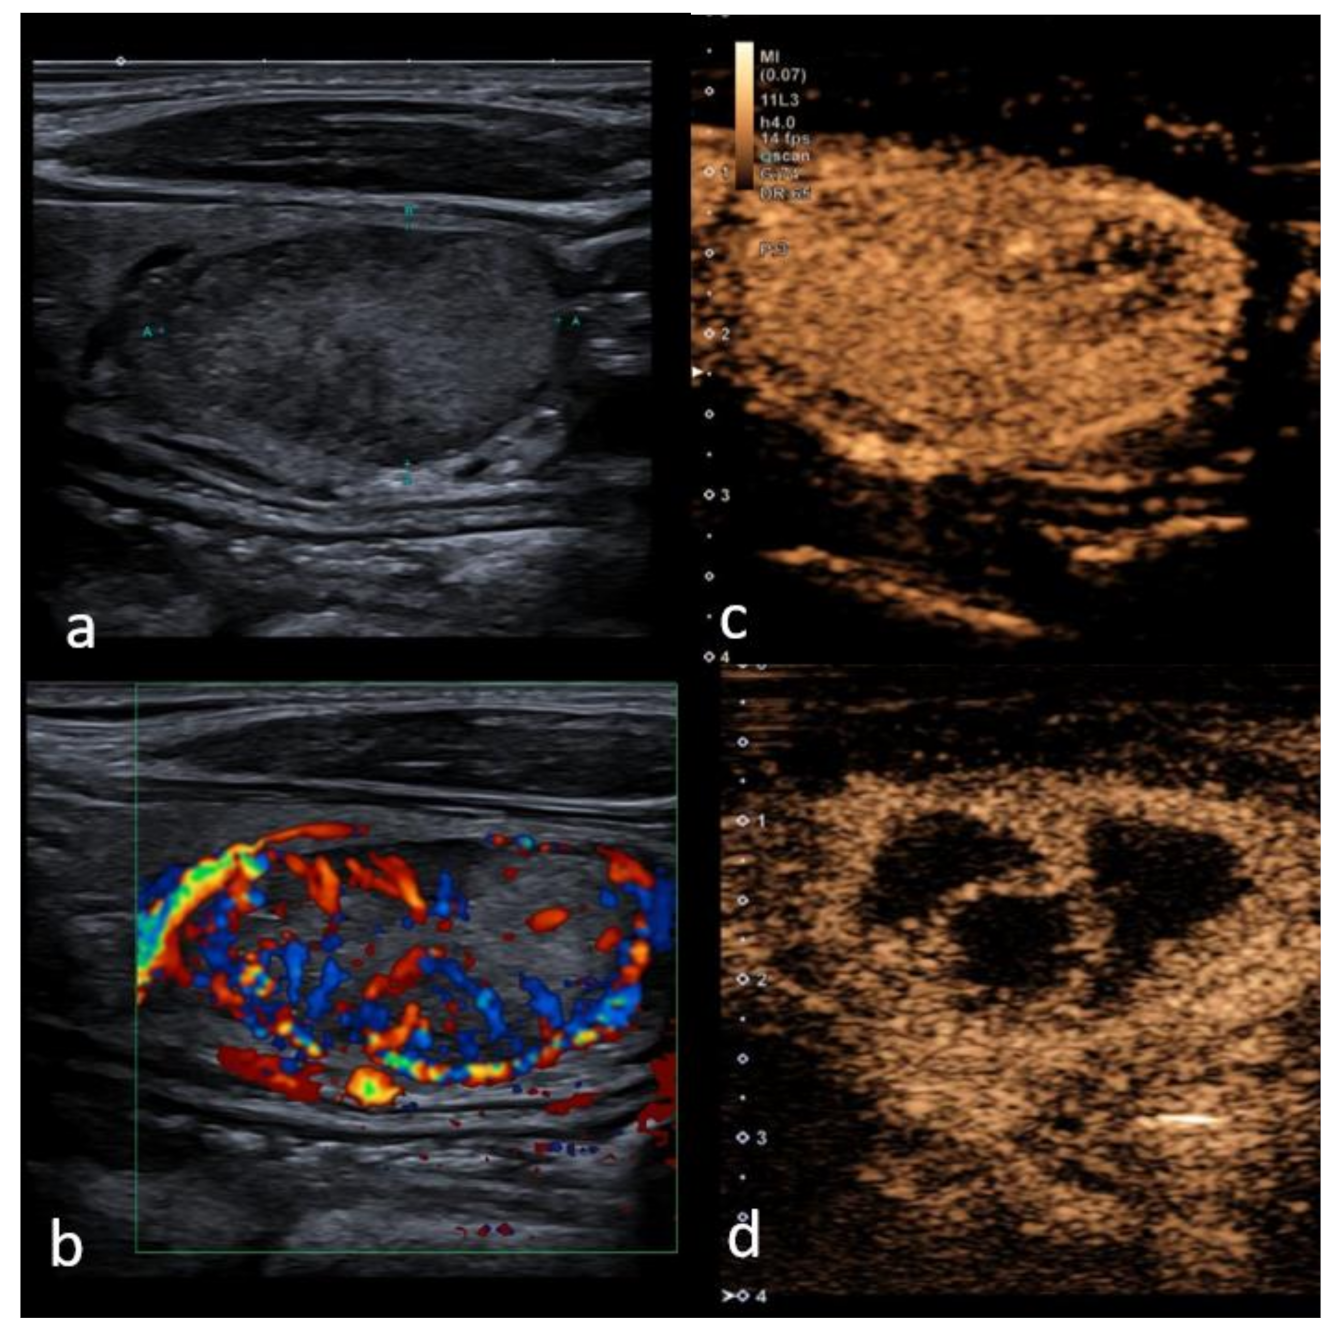

CEUS helps to clarify boundaries between viable and nonviable tissue before and after treatment (Figure 3). This could be helpful in obtaining a more precise and reproducible measurement of the ablated area right after the ablation procedure and in the follow-up imaging—early term (3 months) and intermediate-term (6 and 12 months) are suggested intervals for follow-up with long term monitoring up to 1–2 years, to assess regrowth and to address the misinterpretation of post-treatment appearances (hypo-echogenicity), mimicking malignancy in cases of limited history data [105].